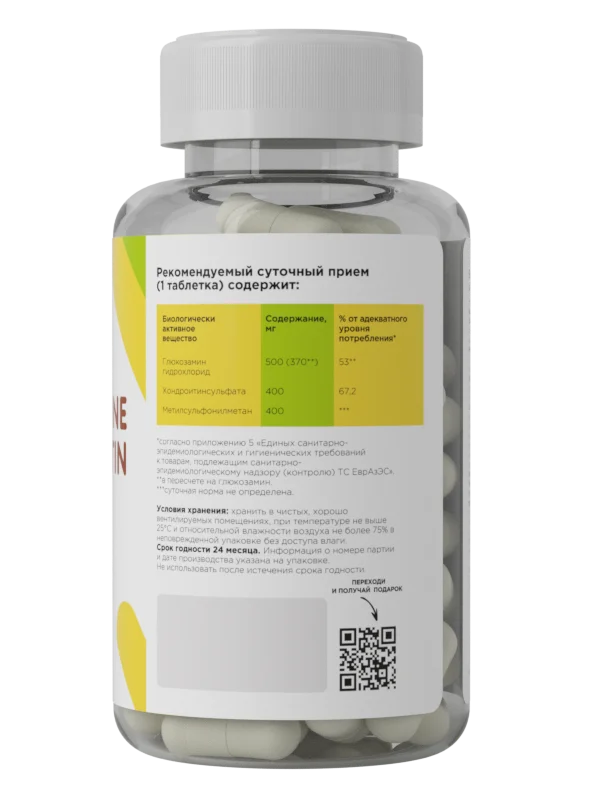

Как видите, выбирать между ними – так себе затея. Исходя из свойств каждой добавки, можно с уверенностью сказать, что лучшие препараты для суставов и связок – это хондропротекторы нового поколения, многокомпонентные. Например, в хондропротекторе от Prime Kraft дополнительно к хондроитину и глюкозамину содержится MСM – метилсульфонилметан, противовоспалительное средство для суставов, которое ускоряет поступление питательных веществ в клеточные мембраны и снижает болевые ощущения в связках и суставах.

Хондропротектор пьют курсами, 1-3 месяца 2-3 раза в год , в зависимости от состояния ваших суставов. По 1 капсуле 1 раз в день во время еды, в восстановительный период после травм и повреждений - 2 раза в день.